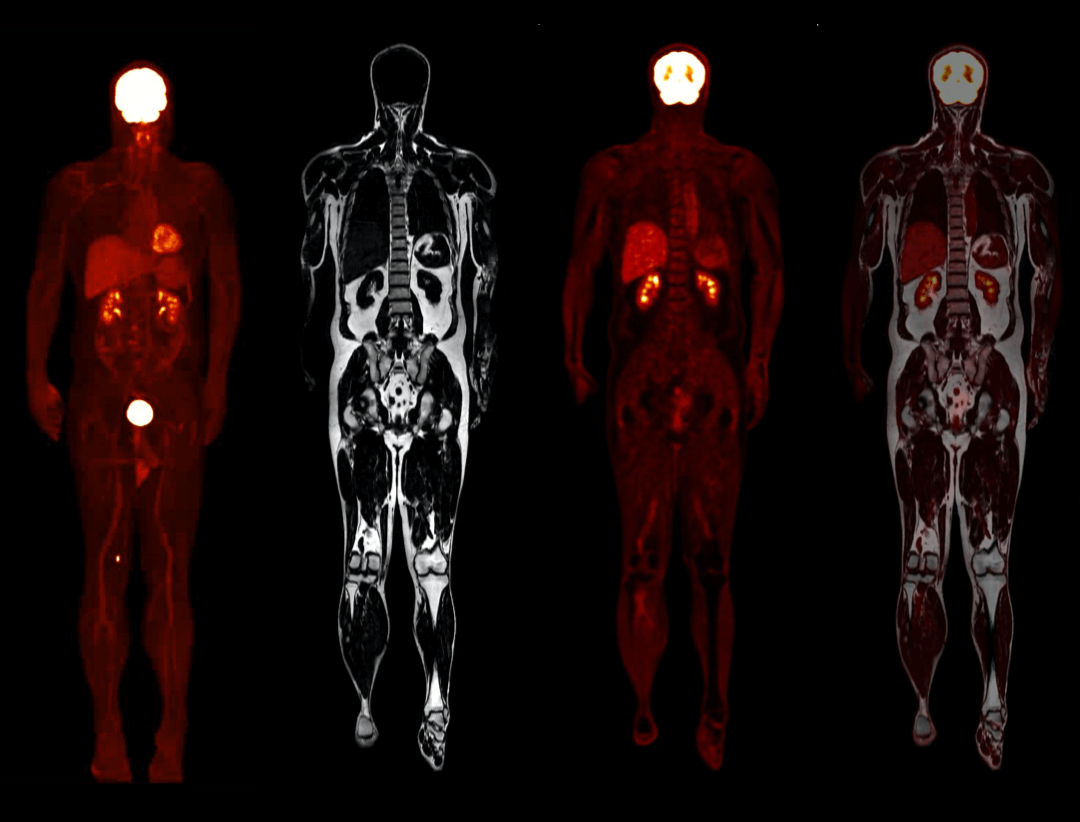

Whole-body Imaging with 4 bodies comparison

Whole-body Imaging